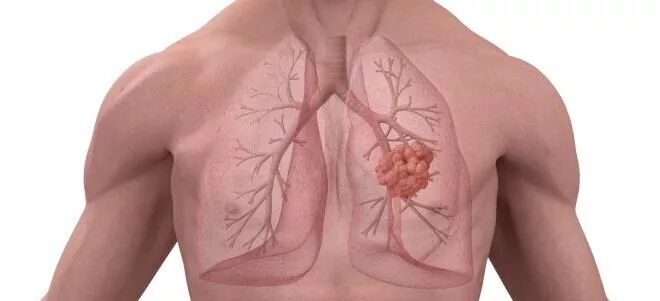

Пневмосклероз легких что это такое симптомы лечение